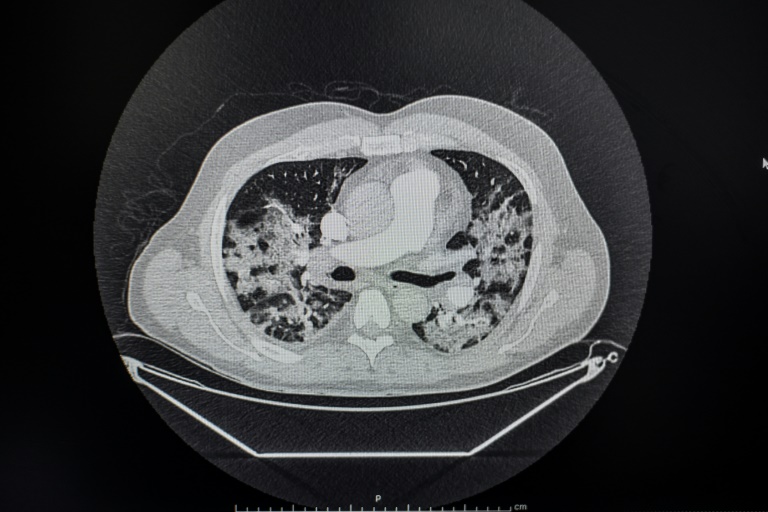

Transporté par le Samu à l’hôpital Cochin, il passe un scanner qui témoigne de lésions pulmonaires, le test nasal PCR confirme qu’il est positif au Covid-19: après une nuit aux urgences, le médecin est transféré en pneumologie et installé sous oxygène, avec un traitement antibiotique d’azythromycine. Le 28 mars, la fièvre restant élevée, les médecins suspectent une embolie pulmonaire et prescrivent un angioscanner - accompagné d’une injection de produit révélateur dans les vaisseaux - qui écarte cette inquiétude. La fièvre finit par tomber. La fameuse vague, redoutée par les soignants, déferle sur l’Ile-de-France après avoir frappé le Grand Est: les bilans explosent, la France compte déjà plus de 5.500 morts et frôle les 7.000 patients en réanimation. La toux persiste, la douleur thoracique aussi, ainsi que des frissons et des tremblements, six à sept jours après avoir quitté l’hôpital. Trois semaines après sa sortie de Cochin, le Dr Vasseur énumère les symptômes qui persistent: